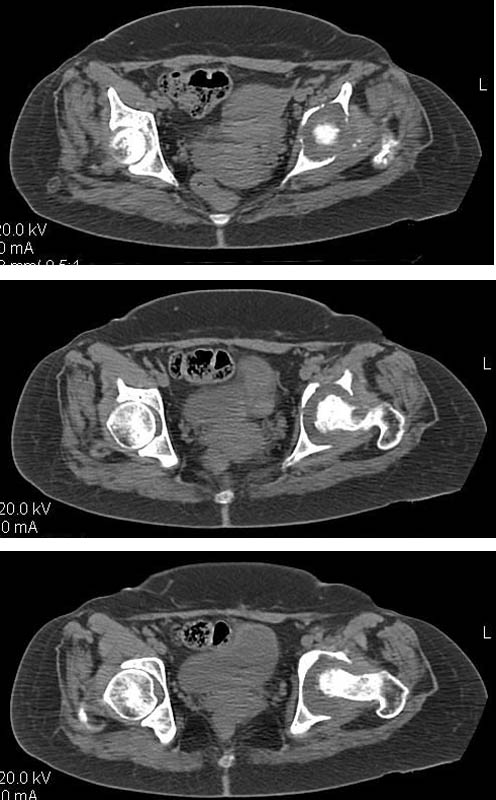

Женщина, 45 лет. В марте перенесла левосторонний коксит неизвестной этиологии. Специфику и онкологию исключили.

Интраартикулярных инъекций не было. Сейчас процесс клинически и рентгенологически - стабилизировался. Состояние вполне удовлетворительное.Предполагается тотальное эндопротезирование с пластикой полости аутокостью. Возможна ли бесцементная <чашка>? Заранее благодарю! С уважением,А.В.Владзимирский

Дополнение - проконсультировался с женой-она специалист рентгенолог - на КТ большое колиество мягкотканного компонента - ищите микоплазмы или бруцеллу. Я склоняюсь к виопсии.

Пртезирование через пол года после коксита закончившегося лизисом сустава, который на снимках выглядит как гнойный? Что значит неизвестной этиологии?